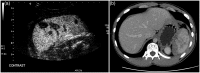

Figure 8.

Splenic trauma. (a) Late-phase CEUS image demonstrating multiple splenic lacerations and intraparenchymal haematomas. (b) Corresponding CT image demonstrating splenic lacerations and perisplenic haematoma.